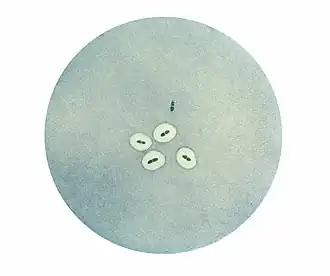

Photomicrographie de plusieurs couples de pneumocoques d'après le test de Neufeld-Quellung. Les pneumocoques semblent "repousser" le colorant, ce qui révèle en réalité l'encombrement de leur capsule par des amas d'anticorps spécifiques de capsules utilisés lors du test, rendant l'accès au colorant impossible. Notez le couple en haut de l'image : défaut de la technique ? Autre espèce de streptocoque ? Forme rugueuse ?

Observé au microscope, le pneumocoque se présente sous forme de diplocoques à Gram positifs lancéolés accolés par leur côté pointu, formant un chiffre 8. Dans les produits pathologiques, les pneumocoques pathogènes sont entourés d'une capsule bien visible[2].

La détermination de type d'un pneumocoque était essentielle à l'époque où la sérothérapie constituait le seul traitement efficace à condition bien sûr d'utiliser le sérum correspondant au type en cause. La méthode la plus simple se fondait sur le phénomène de Neufeld : si l'on émulsionne un pneumocoque encapsulé (produit pathologique ou culture) dans une goutte d'antisérum, on observe un très net épaississement de la capsule si le type de celle-ci correspond au sérum employé.